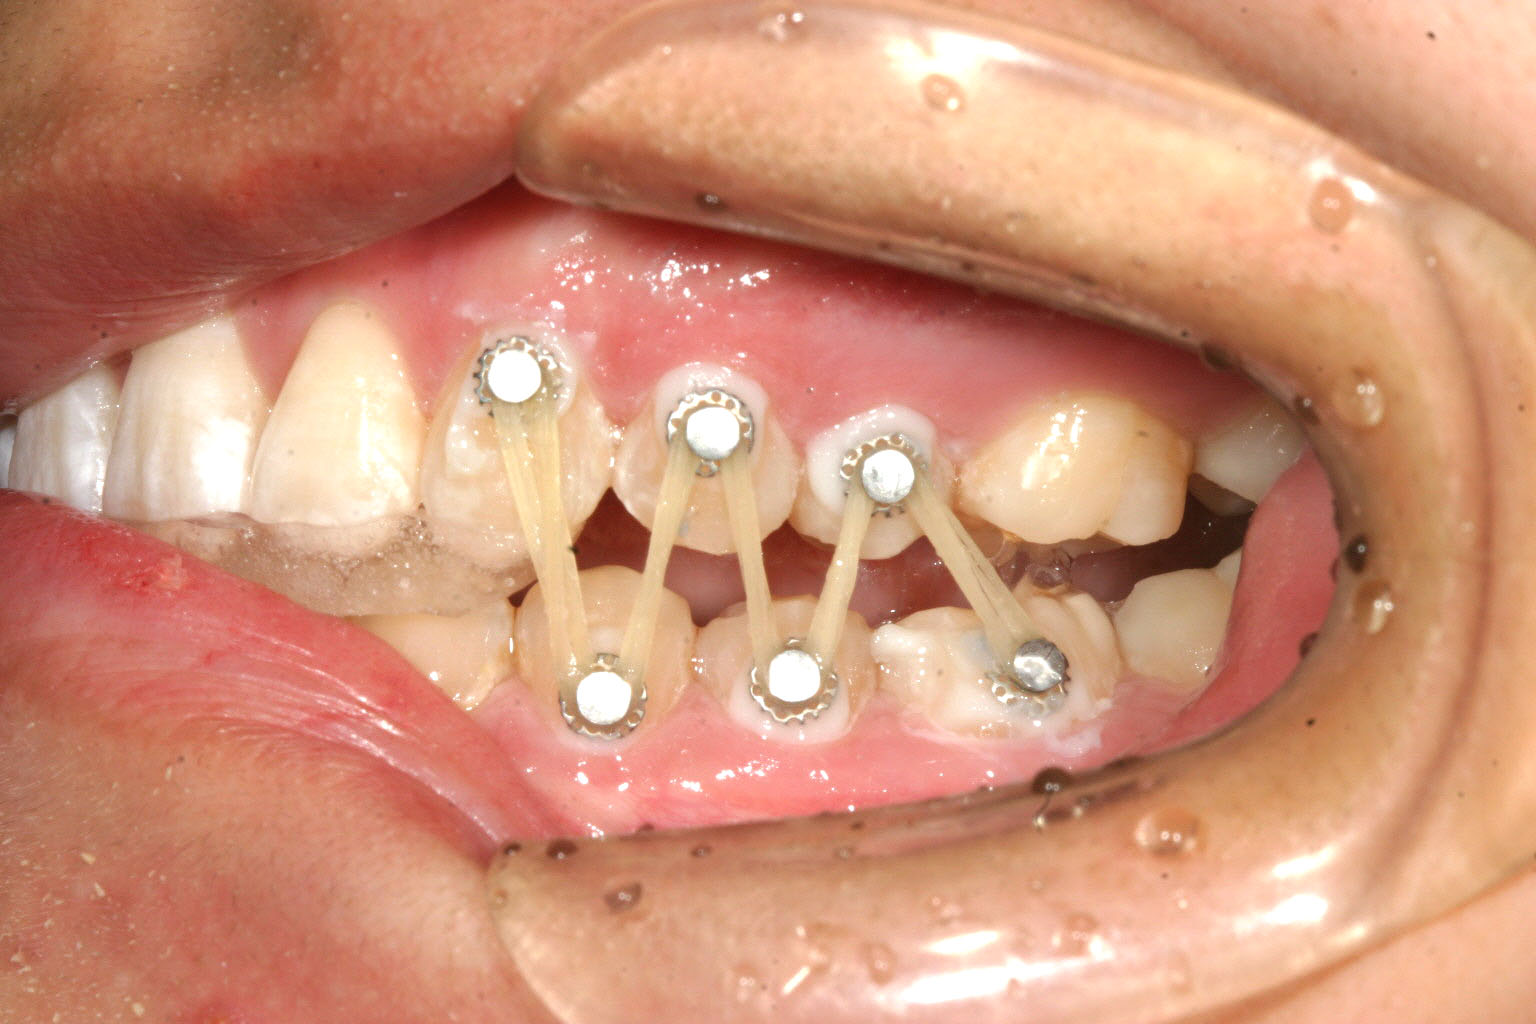

当院独自の自家製装置です。 前歯にジグを噛ませて臼歯に開いた隙間をゴムで閉じます。 この様にする事により結果的に下顎が前方移動し顎関節症が改善します。

今回のケースは顎関節症を伴う不正咬合でよく見かけるかみ合わせですが、上顎前歯が内に入っている為に下顎が後方へ押しやられその結果として顎関節に障害を生じていました。

この様な場合まずインビザラインにて上顎前歯をアーチ上に並べて下顎が前方に移動できる用意が出来たら正常咬合の位置で前歯部を固定する為、ジグを作成しそこで出来た臼歯の隙間をアップダウンエラスティックにて閉じると言う治療を行えば簡単に顎関節症の治療を行う事が出来ます。